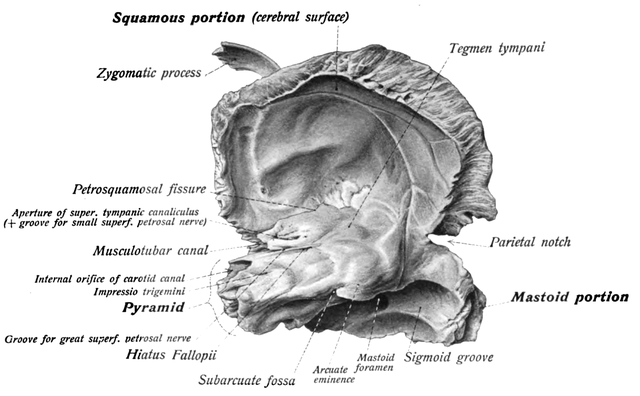

Анатомия и особенности фиссуры петротимпаника